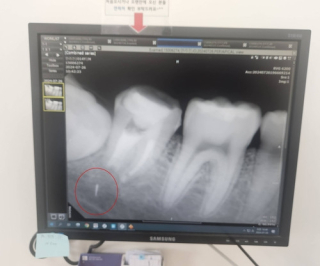

치과 치료 받던 10대 턱에 의료기기 조각 박혀…"평생 이대로 살아야 하는데 합의금 고작 309만원"

치과 치료를 받던 10대 학생의 턱뼈에 의료기기 조각이 박히는 사고가 났다. 2차 피해 우려로 조각을 빼지 못해 평생 이러한 상태로 살아야 하는 상황에서 보험사가 제시한 합의금은 턱없이 낮아 피해자 가족이 ...